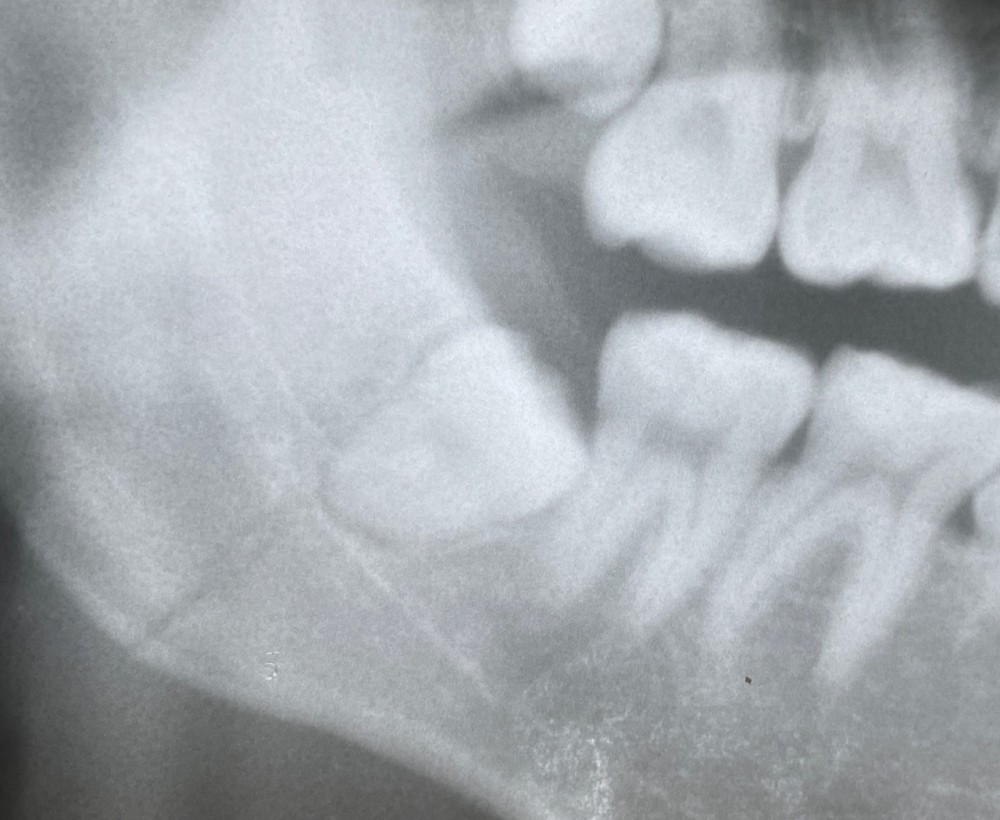

下のエックス線写真は、その6ヶ月後のものです。

骨折ラインは、目立たなくなっていますが、よく見るとまだ確認できます。

親知らずは抜歯されています。